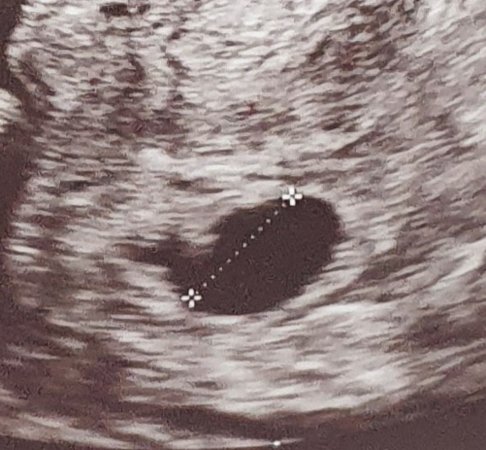

Tässä nyt vielä kuva näkymästä rv 6+0. Ehkä tästä on muille vertailuapua joskus :happy: vasemmalla laidassa nyppylä, joka lääkärin mukaan näyttää alkavalta alkio/istukka-kaiulta. Tosiaan myooma haittasi näkymää eikä varmuutta vielä voitu saada.

Googlailin toki heti miltä tyhjä pussi näyttää ja näyttivät kovin sileäreunaisilta. Ehkä tuo pieni nyppylä tuosta lähtisi kasvamaan ❤

Kyllä tuo hyvältä näyttää, kun vertaan mun keskenmenneeseen, vaikka silloin näkyi syke. Pussi oli pienempi vaikka olin vähän pidemmällä. Varmasti näkyisi syke lähipäivinä :Heartpink